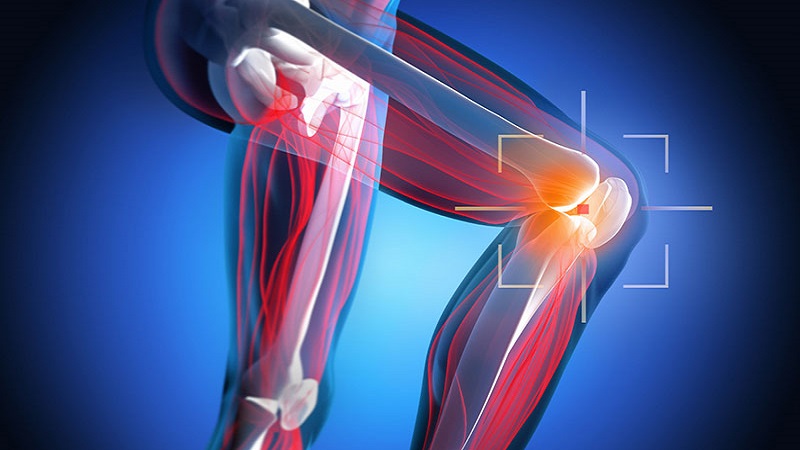

Фото и диагностика кисты Бейкера